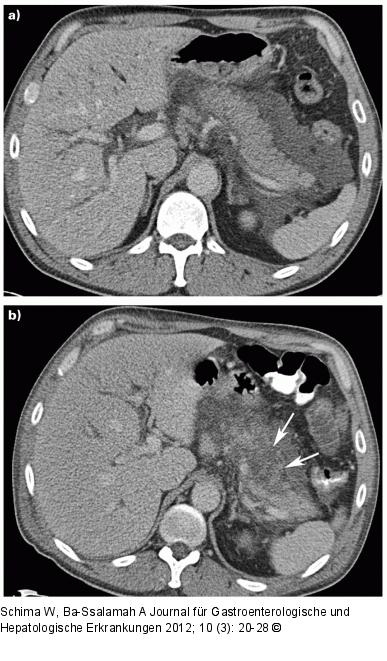

Abbildung 7a-b: Akute Pankreatitis Akute Pankreatitis. (a) Die kontrastmittelverstärkte CT zeigt wenige Stunden nach Beginn der klinischen Symptomatik eine ödematöse Pankreatitis mit peripankreatischen Exsudatstraßen. Das Pankreasparenchym zeigt noch ein homogenes Enhancement. (b) Vier Tage später zeigt die Kontroll-CT eine ausgedehnte Nekrose im Bereich von Pankreas-Corpus und -Cauda (Pfeile), eine relevante Zusatzinformation zu der Ausgangs-CT unmittelbar nach Beginn der klinischen Symptomatik. |

Akute Pankreatitis. (a) Die kontrastmittelverstärkte CT zeigt wenige Stunden nach Beginn der klinischen Symptomatik eine ödematöse Pankreatitis mit peripankreatischen Exsudatstraßen. Das Pankreasparenchym zeigt noch ein homogenes Enhancement. (b) Vier Tage später zeigt die Kontroll-CT eine ausgedehnte Nekrose im Bereich von Pankreas-Corpus und -Cauda (Pfeile), eine relevante Zusatzinformation zu der Ausgangs-CT unmittelbar nach Beginn der klinischen Symptomatik. |